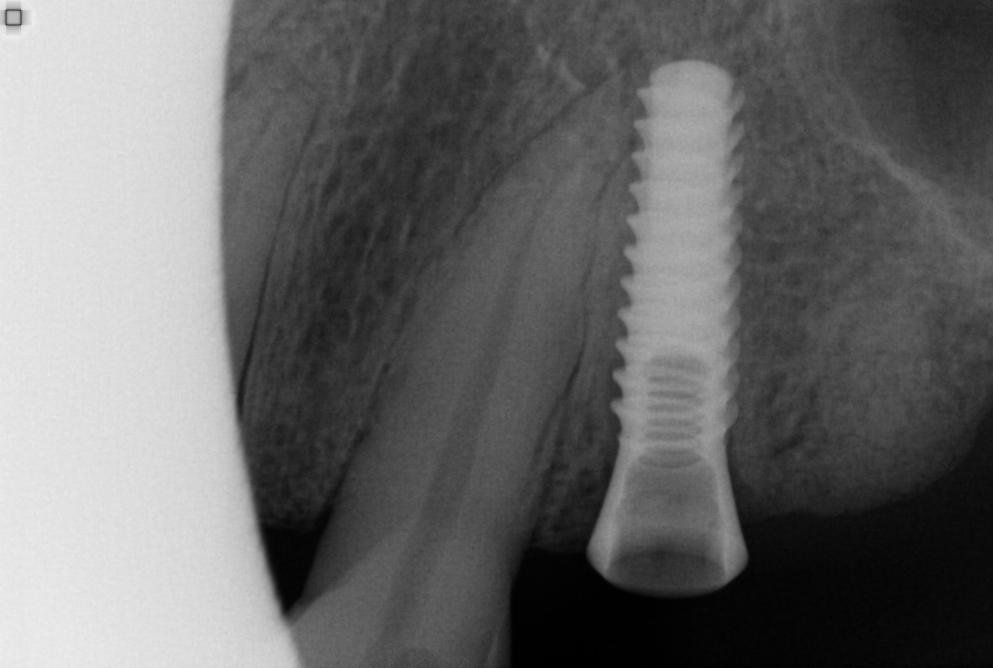

Paciente se presenta a mi consulta con un implante en posición de 2.4 el cual fue colocado hace 7 años y nunca se rehabilitó.